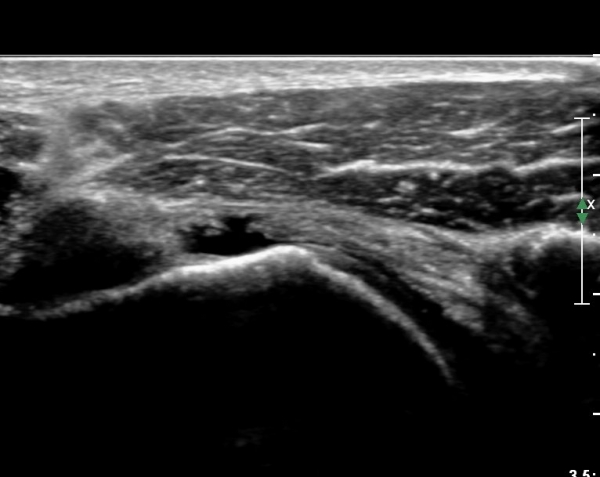

º¸¿© °ß°©ÇÏ±Ù°Ç ÆÄ¿­ÀÌ ÃßÁ¤µÈ´Ù(»çÁø 1). ŽÃËÀÚ¸¦ ¾à°£ ¾Æ·¡·Î À̵¿ÇÑ ÈÄ

ÆÈÀ» ¿ÜȸÀüÇϸ鼭 °üÂûÇÏ´Ï °ß°©ÇÏ±Ù°Ç ÆÄ¿­ÀÌ ¶Ñ·ÈÇÔ(»çÁø 2, 3).